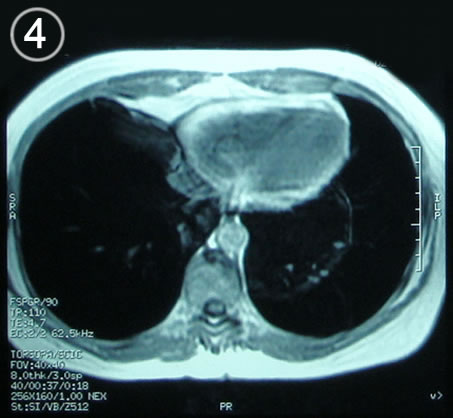

Resonancia Corte axial 3 cardias

Corte Axial en secuencia T1

Corte mediastinico paracardiaco altura del cardias.

La lesión homogénea luce solida bien limitada sin trabeculas o septos

b: cardias  .c: aorta descendente y a su lado derecho el esófago.